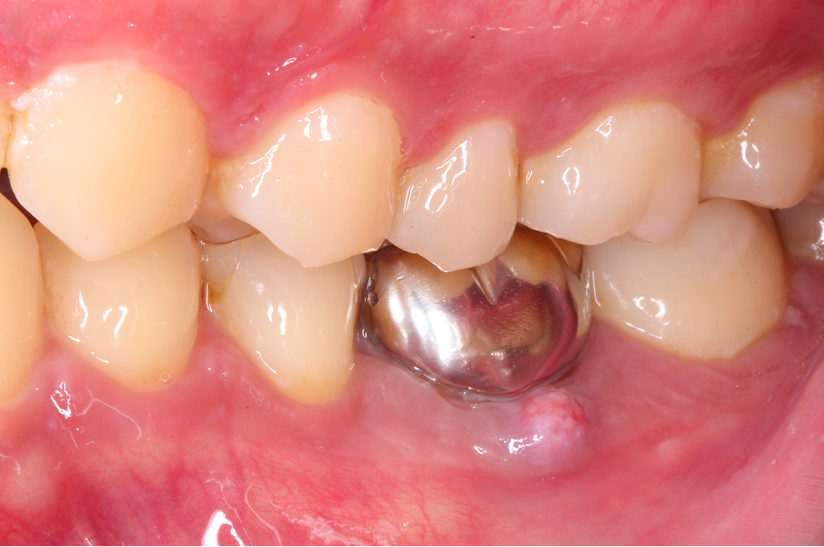

再根管治療で歯を残した症例

タップで写真の拡大ができます。

Before

Under Treatment

Under Treatment<

After

主訴

体調が悪い時に脈打つ感じがする

治療内容

再根管治療(大臼歯)、異物除去、レジンコア

治療期間

1ヶ月

治療費用

220,000

治療の

リスク

処置中に歯肉縁下におよぶ重度のう蝕や破折を認めた場合、治療を中断する可能性があります。術後も症状が残る場合は追加の処置が必要になる可能性があります。